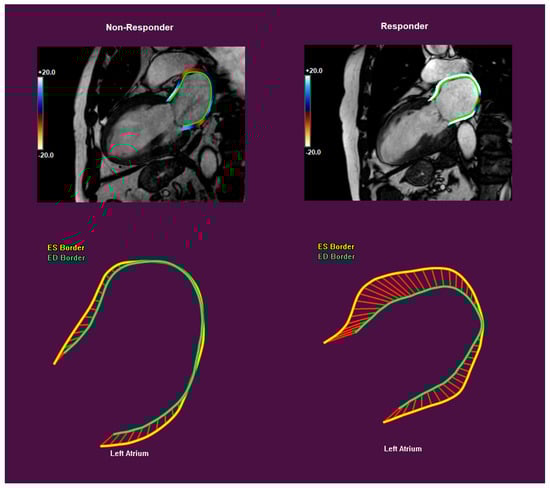

3.2. Strain Measurements and CRT Response

| RV GLS (%) | −22.8 ± 7.4 | −25.0 ± 6.5 | −18.9 ± 7.6 | 0.004 |

| RV free wall GLS (%) | −28.9 ± 8.9 | −31.1 ± 7.9 | −24.9 ± 9.5 | 0.017 |

| LA GLS (%) | 21.6 ± 11.3 | 25.1 ± 10.4 | 15.6 ± 10.4 | 0.002 |

| LA GCS (%) | 24.0 ± 15.0 | 27.9 ± 14.7 | 17.1 ± 13.1 | 0.012 |